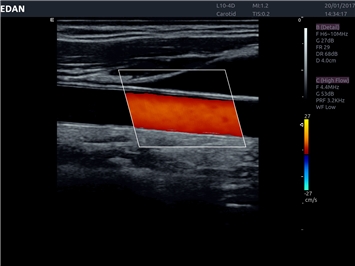

EDAN Acclarix LX4 представляет собой инновационную ультразвуковую систему, построенную на усовершенствованной платформе Acclarix. Сочетание высокого качества визуализации с интеллектуальным рабочим процессом делает эту систему оптимальным выбором для клиник, ценящих эффективность и экономичность.

Области применения:

Система Acclarix LX4 оптимально подходит для:

• Сосудистой диагностики

• Автоматическое измерение толщины интима-медиа

Цветовой допплер:

Да

Дуплексное сканирование: